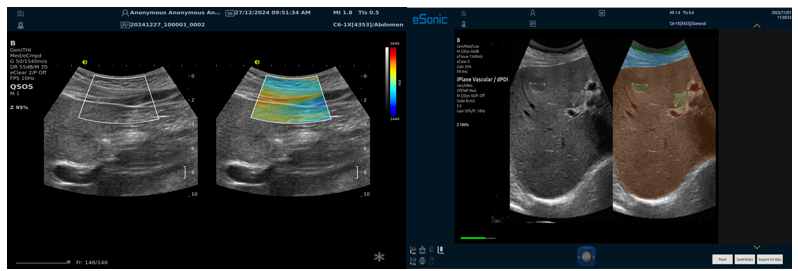

QSOS声速定量成像

测量原理

QSOS声速成像技术利用声波在组织中的传播速度差异性,计算不同位置的声速值,反映组织的物理特性。

成像过程

利用超声探头发射超声波脉冲,分析反射信号的时间延迟,确定声波传播路径和速度,构建声速分布图像。

图像显示

QSOS技术采用彩色编码显示声速图像,不同颜色代表不同声速值,便于医生识别病变部位和测量。

25fb8cb17586b86e5d915a2be3025a2.png

技术优势

?精准定量反映组织特性,成像更敏锐?彩色编码直观显示,轻松发现异常?捕捉声速差异,早期、微小病变更易察觉

肌骨22.png

肌骨领域的应用

?精准定位损伤部位?判断损伤严重程度?监测肌肉营养?评估肌少症?骨质疏松评估

08bce87534cf2cf9f10c1dfc5b314dd.png

NeedleTS?穿刺针智能解决方案

?穿刺针增强显影?智能MAP?无磁导航

为临床医生有创穿刺保驾护航,真正实现精准导航。

5c8590e498a3b927e1f709e192d7ee7.png